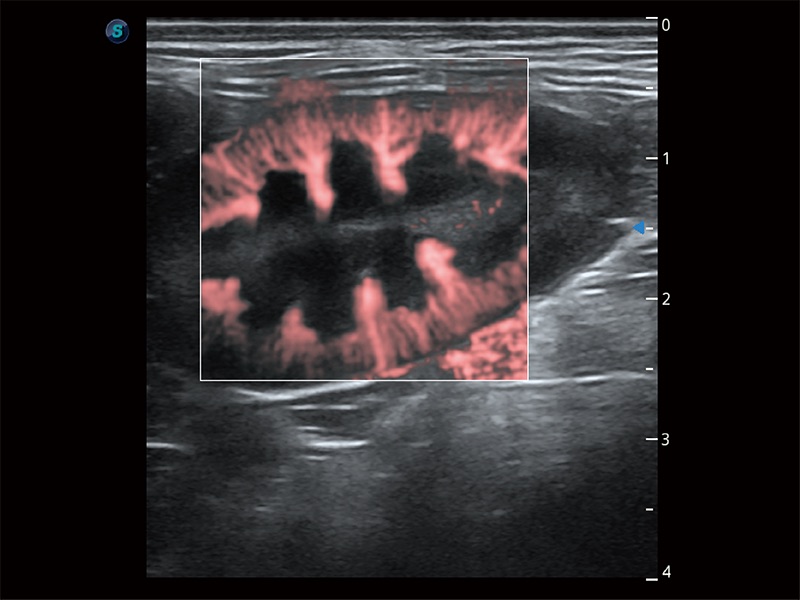

极大提升超低速微细血流的检出能力,同时更精准地滤除软组织和超声信号,为兽用医生提供以往无法通过常规血流获得的疾病诊断信息。

在传统二维血流成像的基础上,呈现血流的立体感,具有动感的生命力之美。即便是微小的血管也能轻松应对,提高了血流的视觉敏感性。

为精细结构及组织边缘提供高清晰度的图像和更大的成像视野。帮助减轻医生的用眼疲劳,快速精准获得测量的数据。